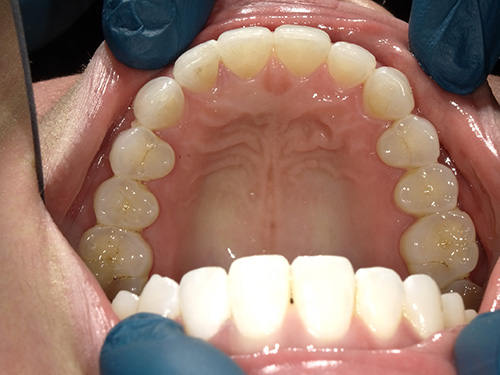

All photos shown below are real patients treated by Dr. Flex — no stock images here. Hover over each image to view the “before” photo and see the amazing results for yourself.